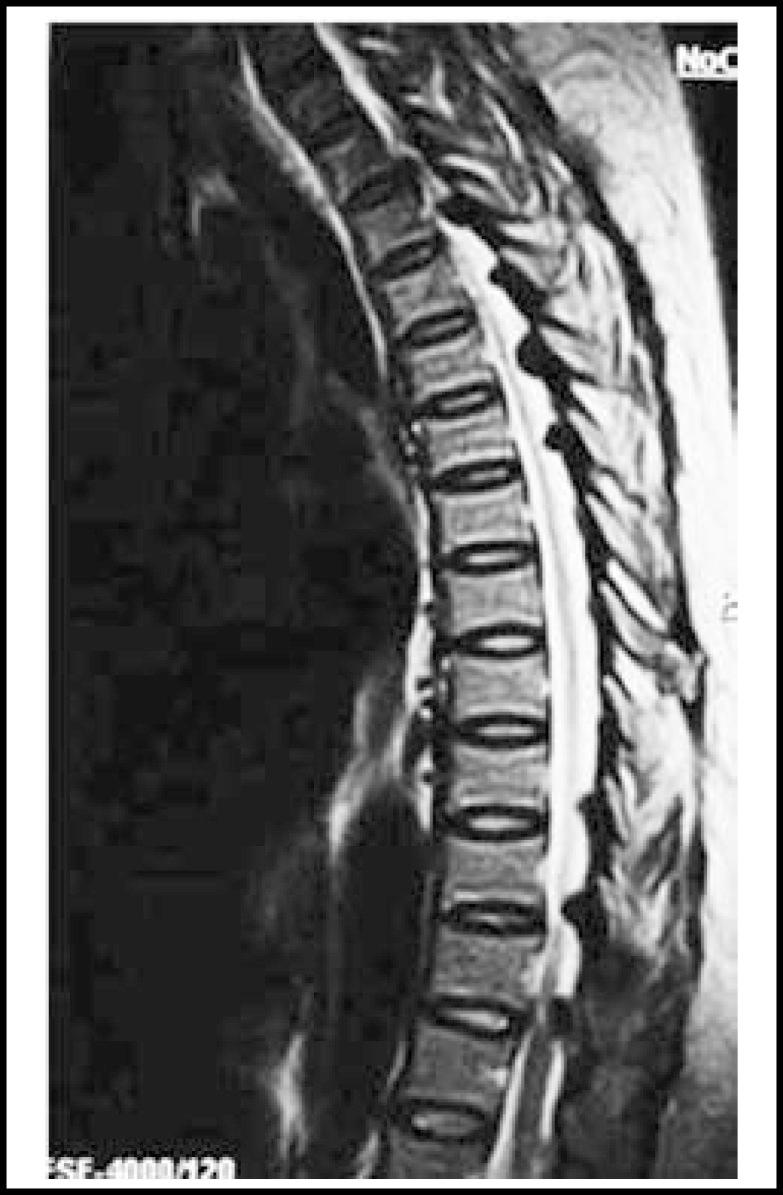

Randomly selected adults from the Village Samorindh, district Tharparker, Sindh, Pakistan, with spinal fluorosis diagnosed on plain x-rays and raised serum fluoride levels were studied from June 2008 to January 2009. MRI was carried out on 0.5 T open magnet MRI system. Features of vertebral body, spinal ligaments, intervertebral disc, facet joints, iliac wings and other incidental findings were noted. Sclerosis was defined as low signal intensity on both T1 and T2 weighted images. RESULTS were described as mean and percentage values.

RESULTS

All the studied 27 subjects complained of back ache without neurological signs. The average age was 43.33 ± 10.45 years; 21 being male (77.8%). The most frequent findings included generalized vertebral sclerosis (24, 88.8%), ligamentum flavum hypertrophy (23, 85%), anterior (20, 74%) and lateral (17, 62.9%) disc herniation, thickened longitudinal ligaments, and narrowing of spinal foramina. Hemangioma was seen in 04(14.8%). The most commonly involved level was L1-2, L4-5 and lower dorsal spine.

CONCLUSION

Vertebral sclerosis, a combination of premature degeneration with anterior disc herniation and an unusually high frequency of vertebral hemangioma formed the spectrum of MRI findings in subjects with spinal fluorosis having back ache but no neurological findings.